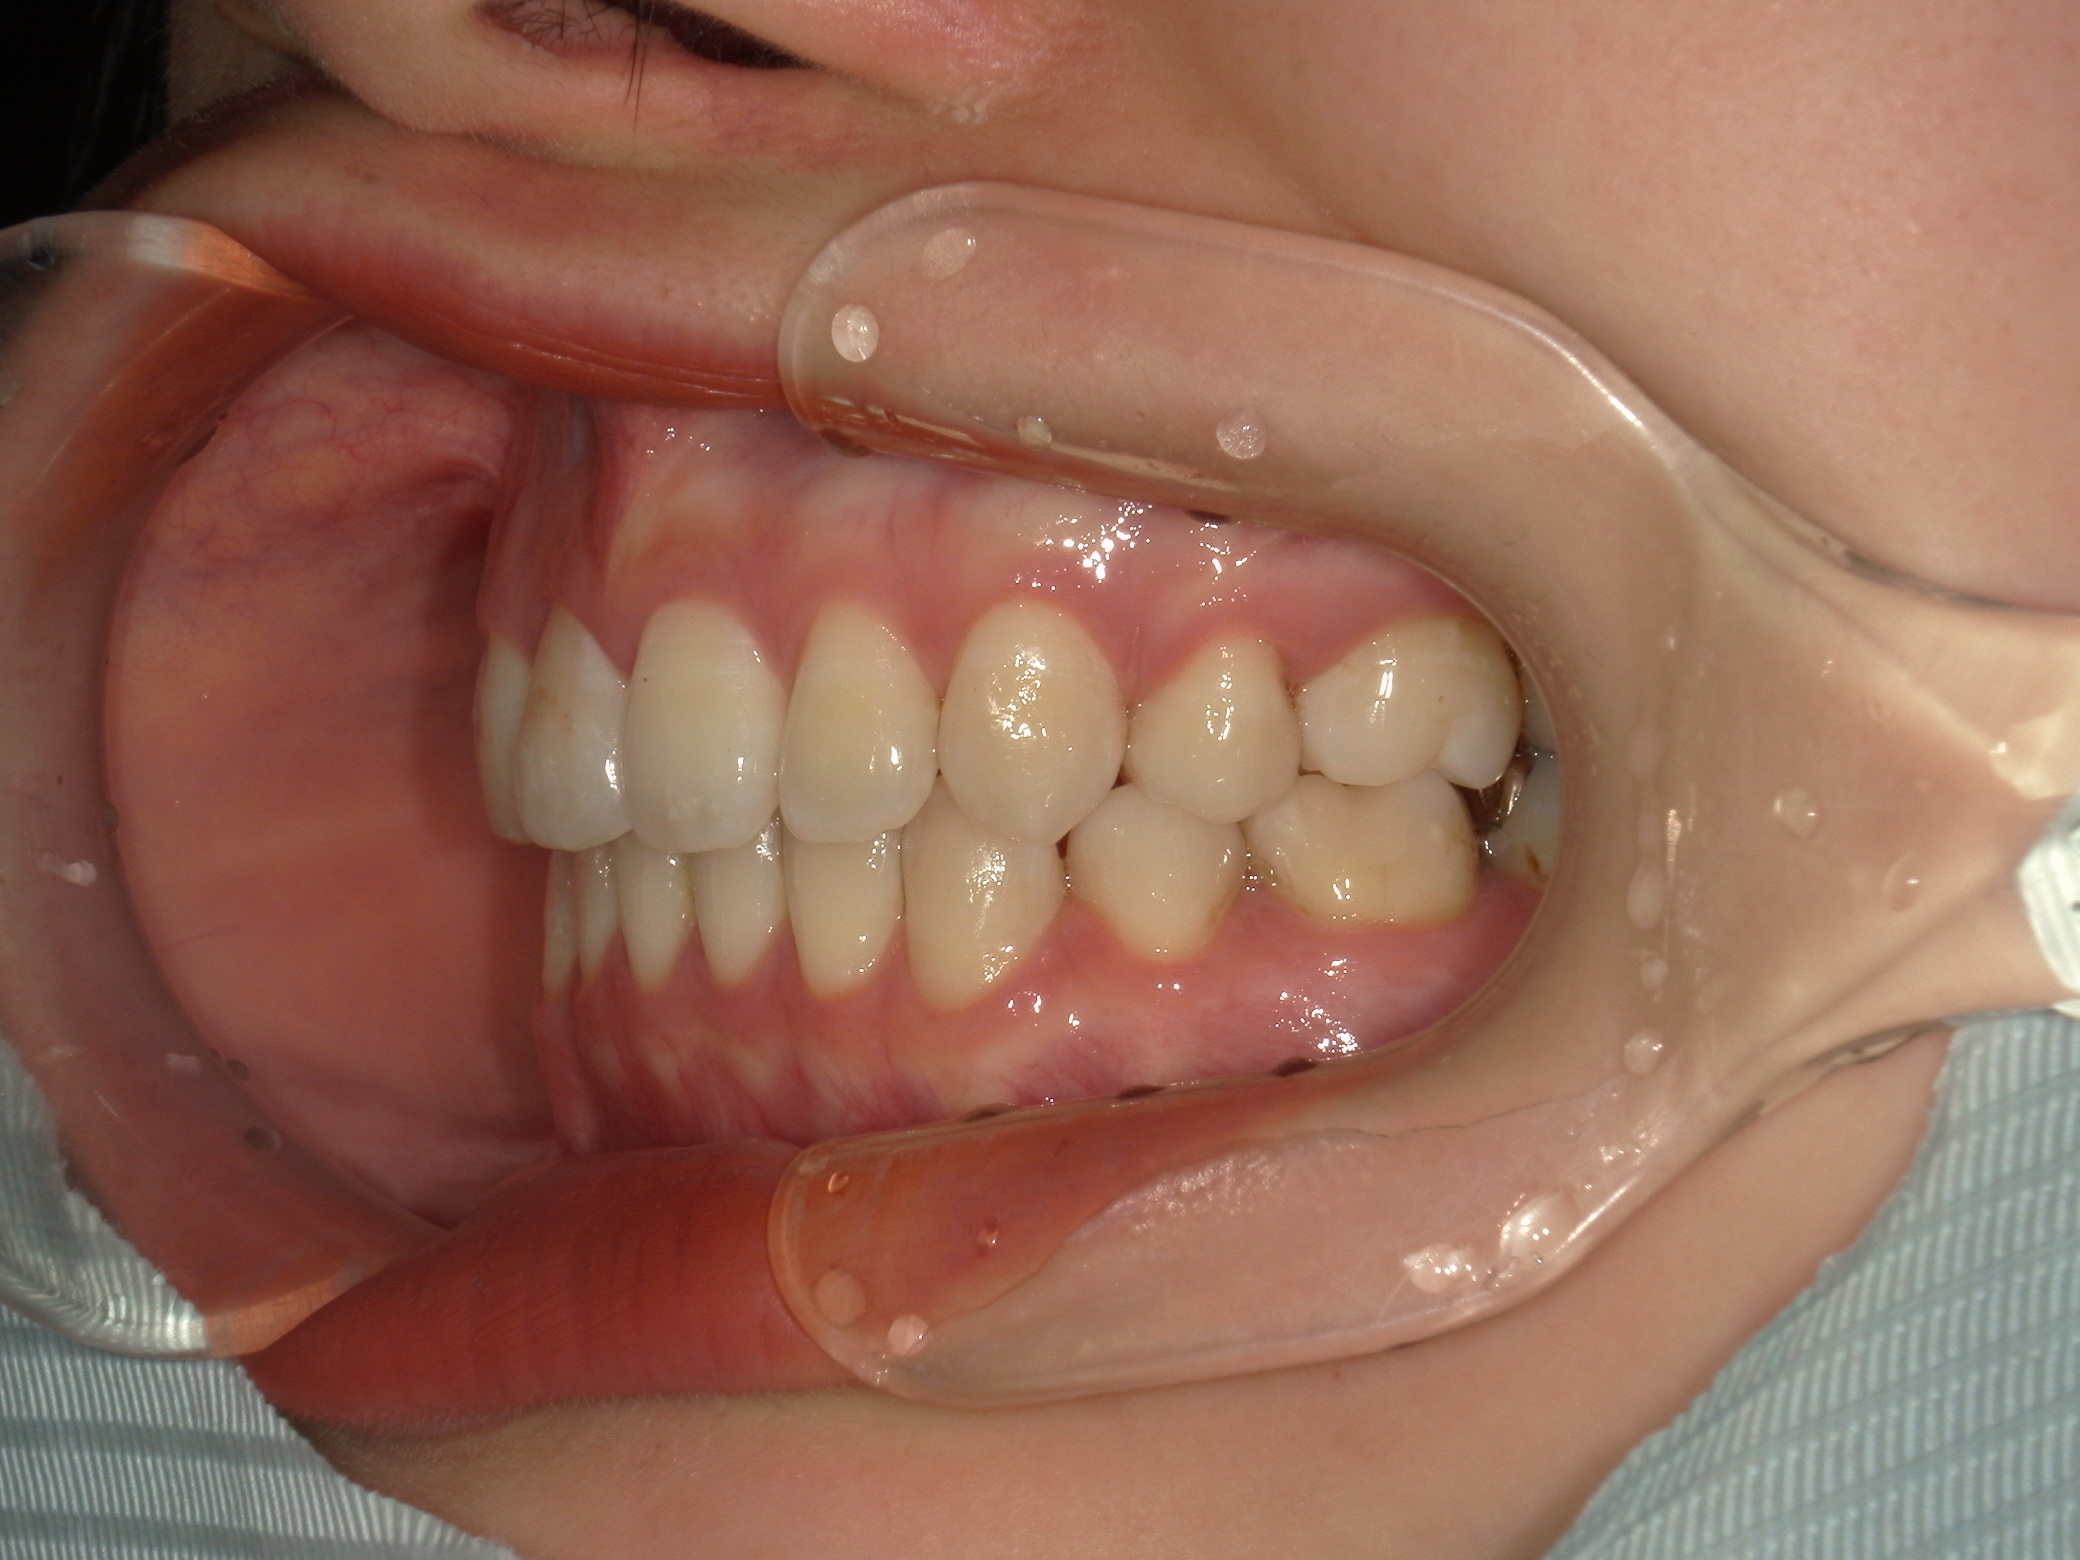

口元の突出を主訴に来院。

上下小臼歯抜歯により突出感を改善する計画を立てた。確立した咬合を崩さないように治療を進める事を目標とした。

患者はハーフリンガル矯正を希望した。

治療後、口元の突出感の改善、咬合関係は維持することができた。